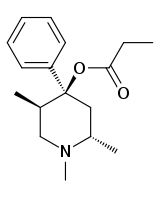

The pharmacodynamic response to an opioid depends upon the receptor to which it binds, its affinity for that receptor, and whether the opioid is an agonist or an antagonist. For example, the supraspinal analgesic properties of the opioid agonist morphine are mediated by activation of the μ1 receptor; respiratory depression and physical dependence by the μ2 receptor; and sedation and spinal analgesia by the κ receptor. Each group of opioid receptors elicits a distinct set of neurological responses, with the receptor subtypes (such as μ1 and μ2 for example) providing even more [measurably] specific responses. Unique to each opioid is its distinct binding affinity to the various classes of opioid receptors (e.g. the μ, κ, and δ opioid receptors are activated at different magnitudes according to the specific receptor binding affinities of the opioid). For example, the opiate alkaloid morphine exhibits high-affinity binding to the μ-opioid receptor, while ketazocine exhibits high affinity to ĸ receptors. It is this combinatorial mechanism that allows for such a wide class of opioids and molecular designs to exist, each with its own unique effect profile. Their individual molecular structure is also responsible for their different duration of action, whereby metabolic breakdown (such as N-dealkylation) is responsible for opioid metabolism.

Phenylpiperidines

- Pethidine (meperidine)

- Ketobemidone

- MPPP

- Allylprodine

- Prodine

- PEPAP

- Promedol